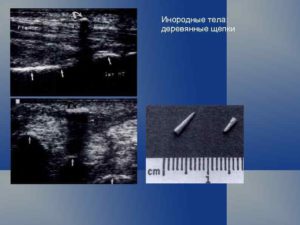

Все ИТ классифицируются как рентген контрастные – видимые на снимке при рентгенографии, малоконтрастные – трудно определяемые на рентгеновском снимке, и рентген неконтрастные – не проявляющиеся при рентгенографии.

Последние могут быть выявлены с помощью ультразвукового исследования.